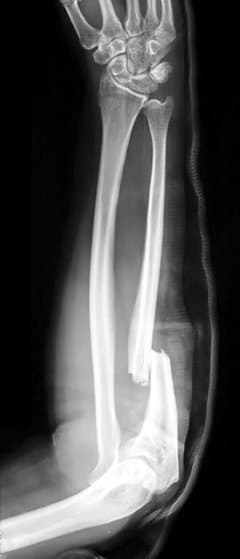

The Monteggia fracture is a fracture of the proximal third of the ulna with dislocation of the proximal head of the radius. It is named after Giovanni Battista Monteggia. Mechanisms include: Fall outstretched hand with the forearm in excessive pronation (hyper-pronation injury). The ulna fractures in the proximal one-third of the shaft due to extreme dislocation. Depending on the impact and forces applied in each direction, degree of energy absorption determines pattern, involvement of the radial head and whether or not open soft tissue occurs. Direct blow on back of upper forearm would be a very uncommon cause. In this context, isolated ulnar shaft fractures are most commonly seen in defence against blunt trauma (e.g. nightstick injury). Such an isolated ulnar shaft fracture is not a Monteggia fracture. It is called a 'nightstick fracture'. There are four types (depending upon displacement of the radial head): I - Extension type (60%) - ulna shaft angulates anteriorly (extends) and radial head dislocates anteriorly. II - Flexion type (15%) - ulna shaft angulates posteriorly (flexes) and radial head dislocates posteriorly. III - Lateral type (20%) - ulna shaft angulates laterally (bent to outside) and radial head dislocates to the side. IV - Combined type (5%) - ulna shaft and radial shaft are both fractured and radial head is dislocated, typically anteriorly. These are known as the Bado types. Monteggia fractures may be managed conservatively in children with closed reduction (resetting and casting), but due to high risk of displacement causing malunion, open reduction internal fixation is typically performed. Osteosynthesis (open reduction and internal fixation) of the ulnar shaft is considered the standard of care in adults. It promotes stability of the radial head dislocation and allows very early mobilisation to prevent stiffness. The elbow joint is particularly susceptible to loss of motion. In children, the results of early treatment are always good, typically normal or nearly so.